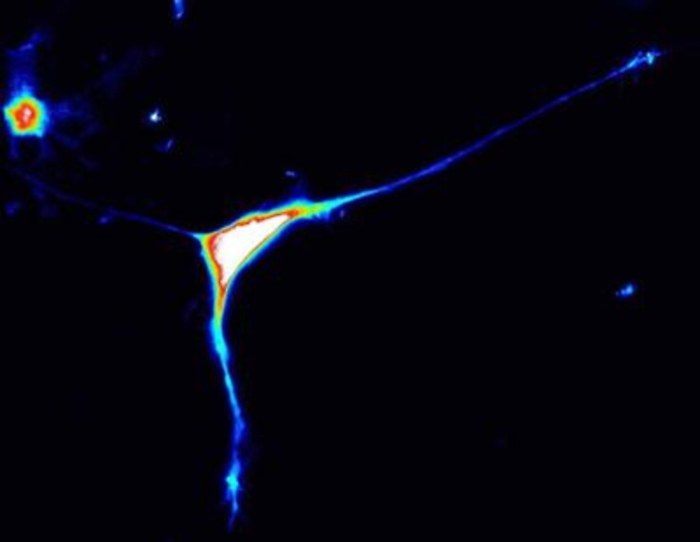

Torino, 13 gen. (Adnkronos Salute) - Importante passo avanti nella comprensione delle basi genetiche dell’autismo: Caprin1 è un nuovo gene responsabile di autismo. E’ quanto emerge dal Progetto NeuroWes di UniTo, uno studio multicentrico internazionale, coordinato da Alfredo Brusco, docente di Genetica medica del Dipartimento di Scienze mediche dell’Università di Torino e della Genetica medica universitaria della Città della Salute di Torino, sviluppato in collaborazione con l’Università di Colonia e recentemente pubblicato sulla rivista scientifica internazionale 'Brain'. Lo studio, basato sulle nuove tecnologie di sequenziamento del Dna e sullo sviluppo di modelli in vitro di cellule neuronali, ha permesso di dimostrare che mutazioni nel gene Caprin1 sono responsabili di alterazioni di specifici meccanismi neuronali che provocano dal punto di vista clinico una forma di disturbo dello spettro autistico. L’uso di tecnologie di sequenziamento dei geni umani, analisi dell’esoma ed analisi del genoma, hanno permesso, infatti, attraverso una collaborazione internazionale di identificare 12 pazienti colpiti da questa forma di disordine del neurosviluppo e comprenderne i meccanismi biologici associati. In particolare, il gruppo di ricerca del progetto NeuroWes, guidato da Alfredo Brusco e Giovanni Battista Ferrero del Dipartimento di Scienze cliniche e biologiche, si è dedicato dal 2015 allo studio della genetica dei disturbi dello spettro autistico, grazie alla collaborazione con molti gruppi italiani e dell’Autism Sequencing Consortium (Asc) alla Icahn School of Medicine, Mount Sinai di New York. L’analisi di centinaia di pazienti ha permesso di individuare un caso piemontese in cui era persa un’ampia regione di un cromosoma che comprendeva il gene Caprin1. Questa iniziale osservazione ha permesso di ipotizzare il ruolo di Caprin1 nella patogenesi dell’autismo e la successiva identificazione di 12 pazienti con una mutazione nel gene ne ha dimostrato il ruolo patogenico. I pazienti mostrano ritardo del linguaggio, disabilità intellettiva, deficit di attenzione ed iperattività, disturbo dello spettro autistico. L’autismo è un frequente disturbo del neurosviluppo che esordisce nei primi anni di vita e colpisce l'1% della popolazione nelle sue varie forme. E' caratterizzato da compromissione dell'interazione sociale, alterazione della comunicazione e interessi limitati, stereotipati e ripetitivi che impediscono di interagire adeguatamente con le persone e l'ambiente.